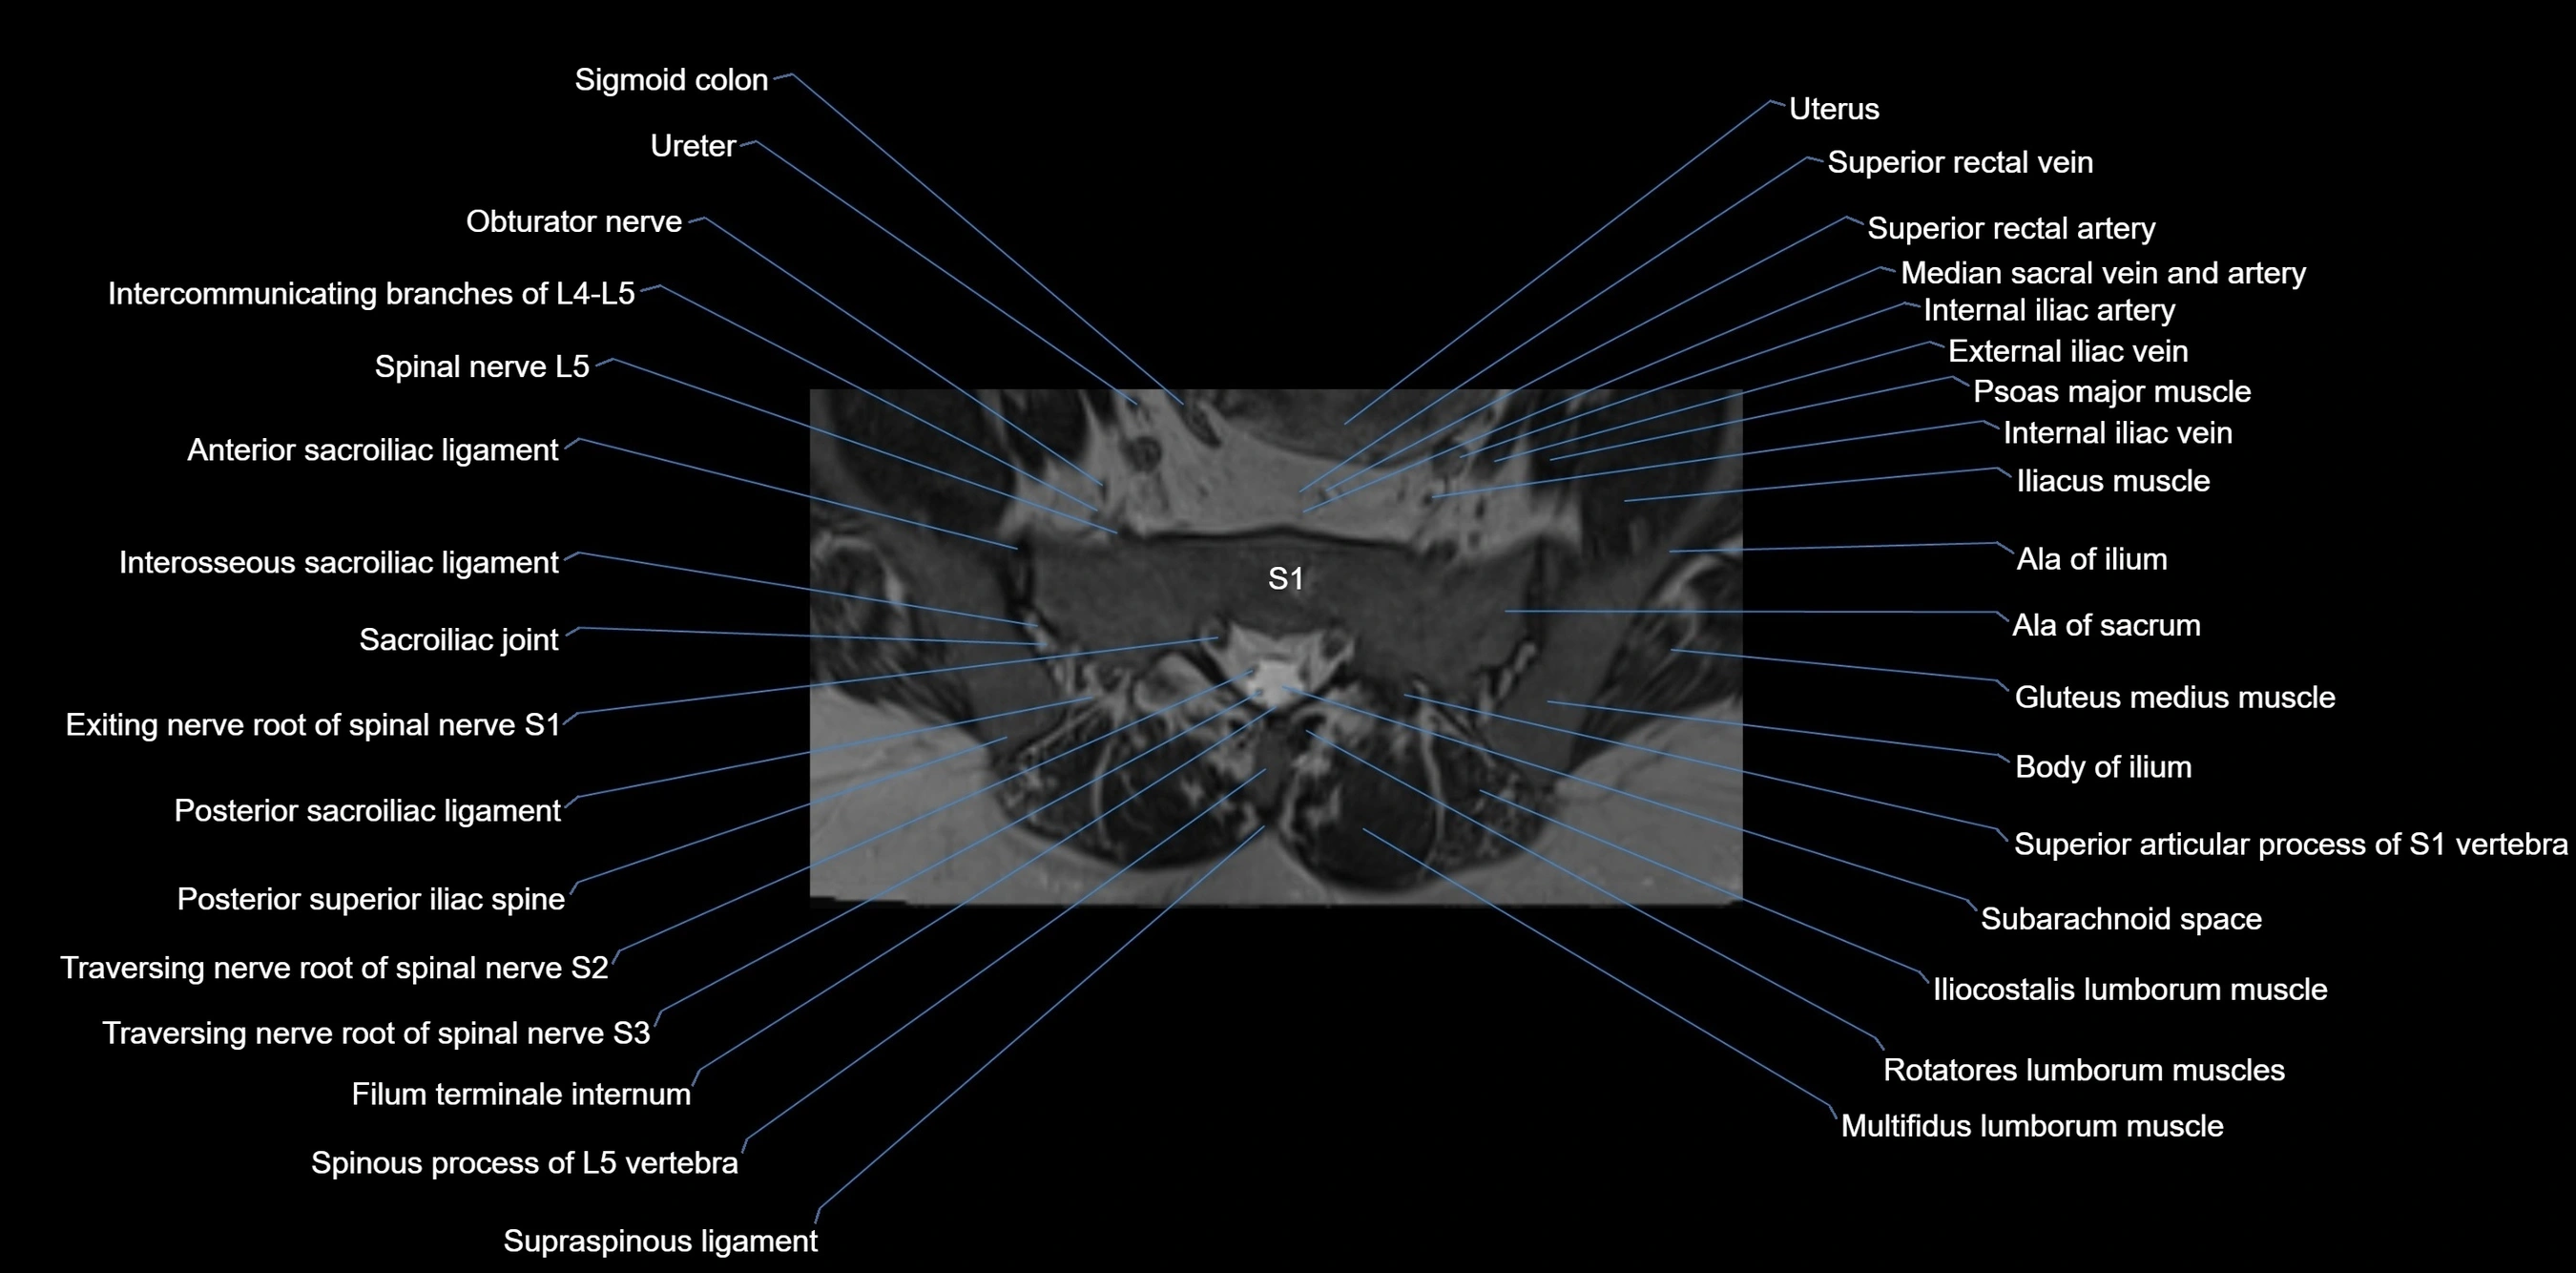

CT VRT image

image